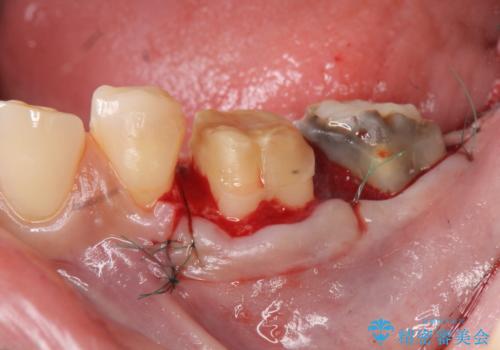

- 著しい歯ぎしりですり減ってしまった、奥歯のクラウンのやりかえを希望され来院されました。

このままの状態でクラウンのやりかえを行うと高さが低く安定の悪いクラウンとなってしまうため、事前に歯周外科手術を行い歯ぐきを下げることで安定性の高いクラウンを製作する治療計画としました。

高さの低いクラウンはセメントが漏出しやすく脱離しやすいだけでなく虫歯の再発の可能性も高まってしまいます。

長期にわたりに安定した環境に整えることで、長く使える可能性を高めることができます。